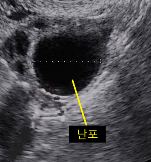

난포의 초음파 소견

그럼 초음파를 보면 배란일을 무조건 추정할 수 있나요?

그렇지는 않습니다. 난포의 모습이 난소낭종(ovarian cyst)로 유사한 경우도 있기도 하고, 난포가 배란되지 않을 수 있어서 초음파가 100% 예측할 수 있다고 할 수는 없겠습니다.